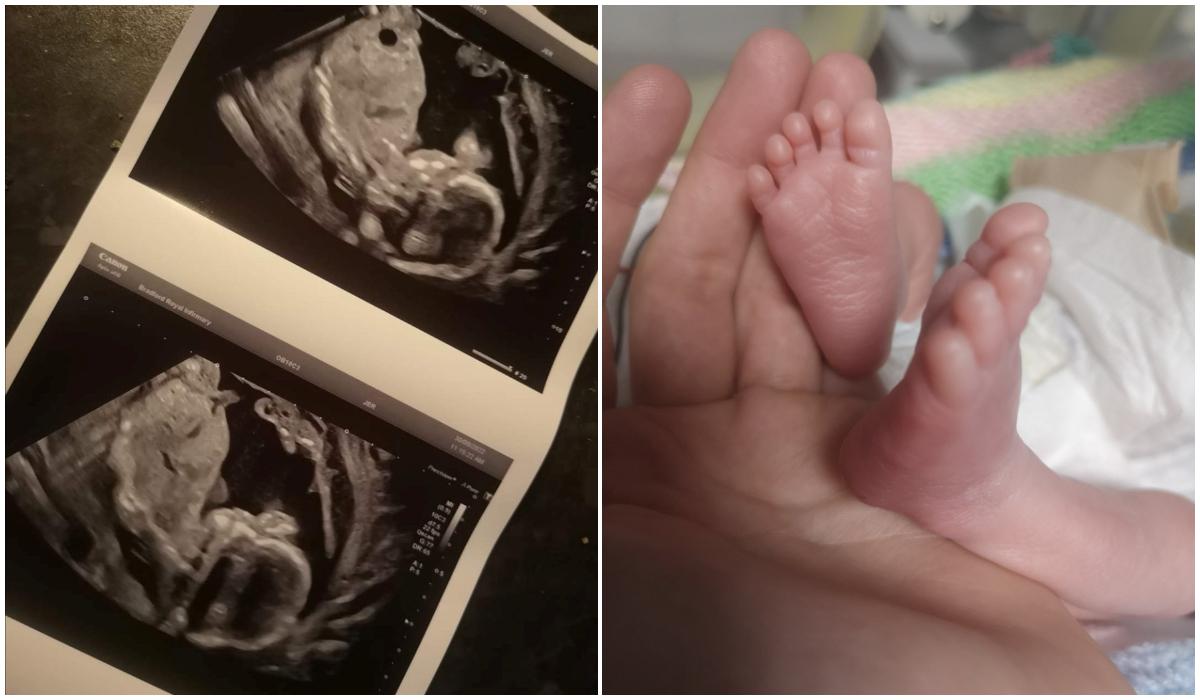

O tânără în vârstă de 27 de ani din UK a avut parte de adevărat un miracol de Crăciun. Chiar dacă medicii i-au spus că bebelușul s-a stins din viață în pântece, aceasta a devenit mamă. Proaspăta mămică susține că este cu adevărat o minune că fiul ei trăiește.

Hannah Cole, o tânără în vârstă de 27 de ani, a fost transportată de urgență la spital, fiind însărcinată în 20 de săptămâni. Acolo, medicii au anunțat-o că fiul ei s-a stins din viață în pântece. Vestea teribilă a venit după ce specialiștii nu au putut detecta bătăile inimii ale micuțului.

În momentul în care a auzit vestea oribilă, tânăra a izbucnit în lacrimi, doar că nu s-a dat bătută. Aceasta a insistat ca medicii să-i facă o nouă ecografie, sperând totuși că fiul ei este în viață. Fără ca cineva să se aștepte, a avut loc un adevărat miracol.

Micuțul Oakley Cole-Fowler a fost adus pe lume în luna octombrie, la doar 24 de săptămâni și trei zile, având o greutate de doar 780 de grame.

Acesta a suferit o operație la intestin când avea opt zile, iar acum este încă în spital. Băiețelul va sta internat până în luna februarie a anului viitor, iar până atunci va mai avea nevoie de câteva intervenții chirurgicale, potrivit jurnaliștilor  The Sun.

În urma celor întâmplate, proaspăta mămică a declarat:   "Sunt atât de ușurată. A fost un adevărat rollercoaster. El este miracolul meu de Crăciun. A fost absolut uimitor de când s-a născut. A evoluat cu pași repezi și abia aștept să îl duc acasă".

În luna octombrie, conducerea unității medicală, acolo unde tânăra a născut, au demarat o anchetă și au prezentat scuze pentru" suferința și anxietatea" cauzate de diagnosticul inițial.